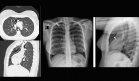

Una radiografía de tórax reveló una masa pulmonar en el lóbulo superior derecho de aproximadamente 5,5 cm de diámetro, con márgenes parcialmente mal definidos, lo que generó sospecha de una lesión neoplásica o infecciosa.

Para evaluar la masa pulmonar observada en la radiografía, se solicitó una tomografía computarizada (TC) de tórax. La TC mostró una masa hipodensa en el segmento anterior del lóbulo superior derecho, que se extendía hacia la pared torácica, afectando el primer y segundo arcos costales y los músculos pectorales.

Además, se identificaron cambios inflamatorios y pequeñas colecciones hipodensas compatibles con un absceso, en relación con una costocondritis séptica de la primera costilla derecha.

Tres meses después del inicio del cuadro clínico, se realizó un TC de control que mostró la resolución del absceso, dejando una pequeña imagen nodular residual de 2 cm en la articulación condroesternal, compatible con cambios cicatriciales.